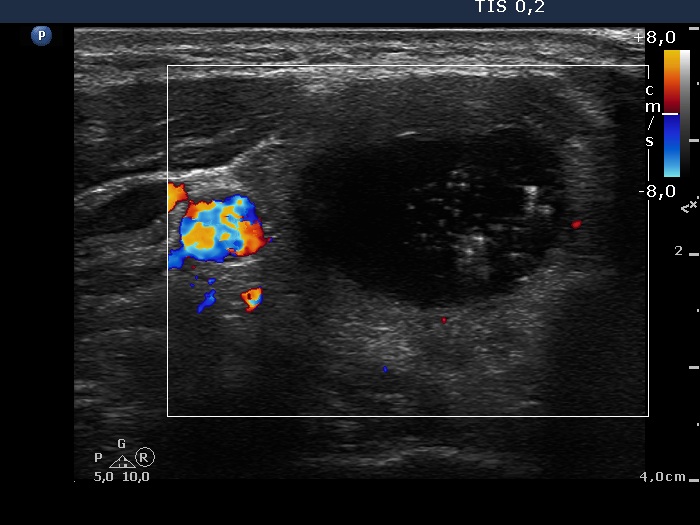

Intranodular hyperechogenic figures - case 624 (ultrasonographic picture 6)

Right lobe, transverse view, color Doppler mode. This nodule lacks blood flow on Doppler mode.